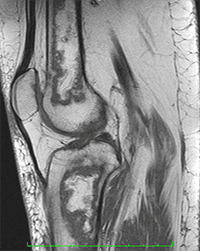

Paciente do sexo feminino, com 53 anos e quadro de dor crônica no joelho direito, principalmente na face anterior e medial. Ela refere piora da dor há uma semana, apresentando dificuldade na deambulação. Nega trauma e relata ter se submetido à cirurgia no tornozelo direito. Refere tratamento para asma brônquica com corticoide há anos.

Exames de imagem